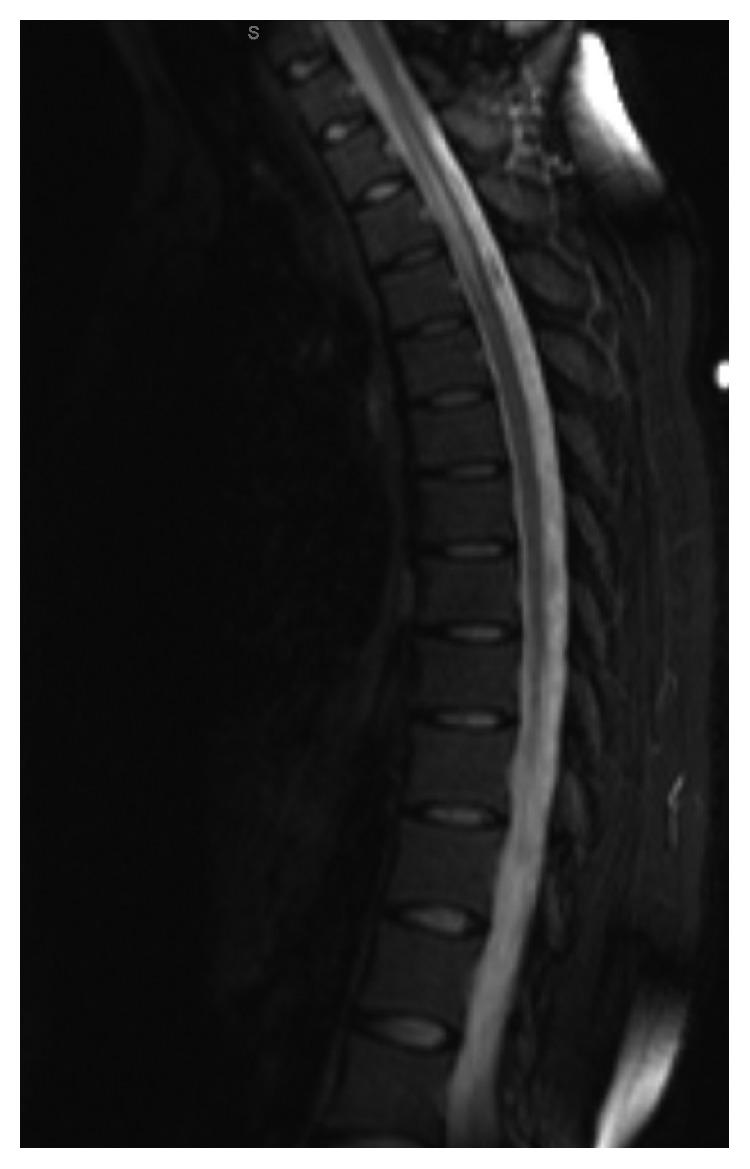

There is a scarceness of information on the central nervous system effects of common variable immunodeficiency (CVID). A 30-year-old woman with a history of recurrent upper respiratory infections, vitiligo, and immune thrombocytopenic purpura presented with right-sided numbness. Magnetic resonance imaging (MRI) of the thoracic spine revealed a signal hyperintensity. MRI of the brain demonstrated FLAIR hyperintensity in the right middle frontal gyrus. Cerebral spinal fluid was unremarkable. Serum immunoglobulins revealed hypogammaglobulinemia. Endobronchial and subsequent mediastinum biopsies were all negative for sarcoidosis and malignancy. No infectious etiology was found. She was treated with glucocorticoids and intravenous immunoglobulin (IVIG) replacement therapy for CVID-associated myelitis. Follow-up MRI showed improvement; however, her numbness persisted despite these treatments, which led to an outside physician adding methotrexate for their suspicion of sarcoidosis. Her symptoms remained stable for two years, but when the methotrexate dose was weaned, her numbness worsened. Upon review, the treatment team refuted the diagnosis of sarcoidosis but continued treatment with prednisone, IVIG, and methotrexate for CVID-associated myelitis, from which her symptoms have stabilized. Here, we discuss CVID-associated neurological complications, its similarities to sarcoidosis, and a literature review with treatment regimens and outcomes.

关于普通可变免疫缺陷(CVID)对中枢神经系统影响的信息匮乏。一名30岁女性,有反复上呼吸道感染、白癜风和免疫性血小板减少性紫癜病史,出现右侧麻木。胸椎磁共振成像(MRI)显示信号高强化。脑部MRI显示右侧额中回FLAIR高强化。脑脊液检查无异常。血清免疫球蛋白显示低丙种球蛋白血症。支气管内及随后的纵隔活检均未发现结节病和恶性肿瘤。未发现感染病因。她因CVID相关脊髓炎接受了糖皮质激素和静脉注射免疫球蛋白(IVIG)替代治疗。随访MRI显示有所改善;然而,尽管进行了这些治疗,她的麻木仍持续存在,这导致外部医生因怀疑结节病而加用甲氨蝶呤。她的症状稳定了两年,但当甲氨蝶呤剂量逐渐减停时,她的麻木加重。经复查,治疗团队否定了结节病的诊断,但继续使用泼尼松、IVIG和甲氨蝶呤治疗CVID相关脊髓炎,此后她的症状已稳定。在此,我们讨论CVID相关的神经系统并发症、其与结节病的相似之处,并对治疗方案和结果进行文献综述。